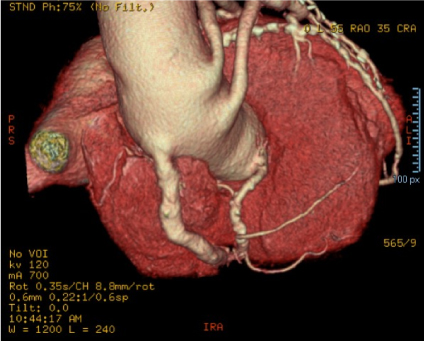

The patient EDAV, with 68-years old, due to coronary artery disease received saphenous grafts. After the last angiotomography of the coronary arteries by computed tomography performed in 2019, May-21, aortic root ectasia was measured, measuring 39 × 40 × 42 mm and GASV, as well as mural atheromatosis in the thoracic aorta, as shown in Figures 1, Figure 2 and Figure 3.

Figure 1: Angiotomography examination of the coronary arteries, showing the saphenous vein aneurysm grafted by the angle of observation 1. View Figure 1